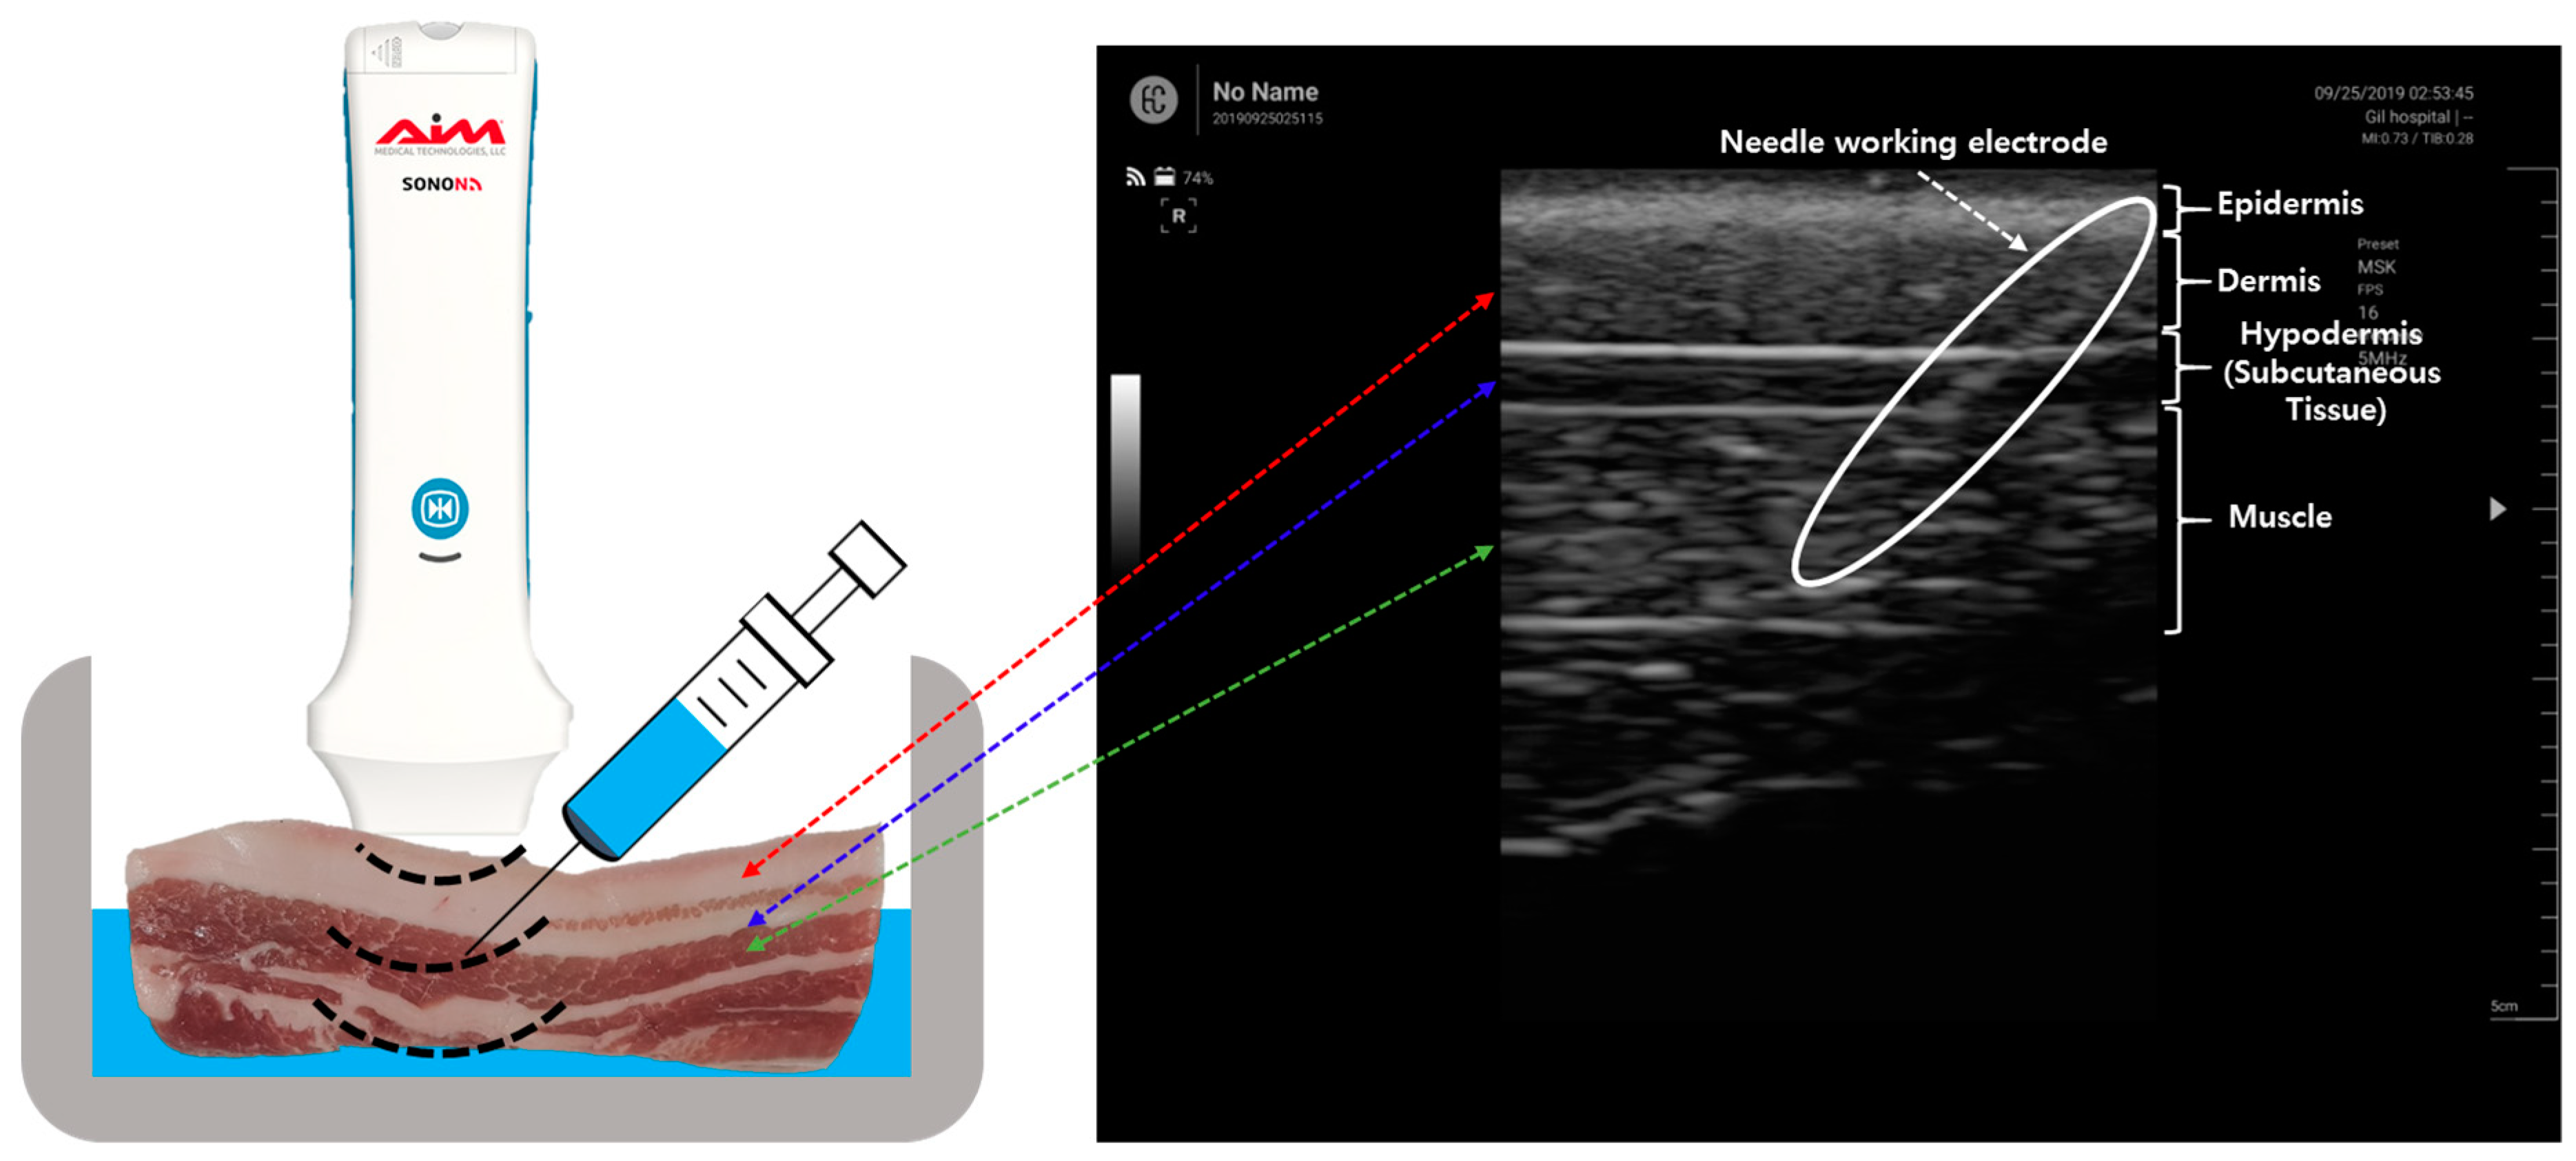

2.2. Electrical Impedance Measurement of Porcine Tissues